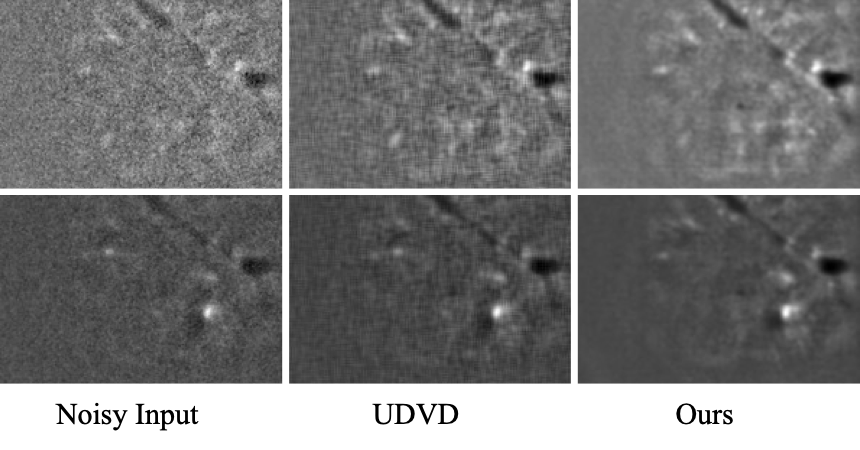

A visual comparison between our method and UDVD on the highly noisy calcium imaging sequences further underscores our superior performance, as shown in Fig. 4. In the noisy frames, it can be challenging to distinguish individual cells due to high levels of noise. UDVD, while effective in reducing some noise, often blurs the intricate cellular structures, making it difficult to identify individual cells.

In contrast, our approach not only removes the noise effectively but also preserves the intricate cellular structures, allowing for better visualization and identification of individual cells. This difference is particularly notable in regions with a high density of cells, where our method is able to maintain the distinct boundaries between cells, whereas UDVD tends to blur them together. This visual comparison highlights our method’s ability to handle real-world data with significant noise, offering promising potential for applications in biological and medical imaging.

Refer to caption

Figure 4: Visual comparison on calcium imaging sequences: The left column shows the original noisy frames, the middle column represents the denoising results from UDVD, and the right column presents the results from our method. It is evident from the comparison that our method is superior at noise reduction, while also maintaining the detailed cellular structures, thereby enhancing the visualization and identification of individual cells.